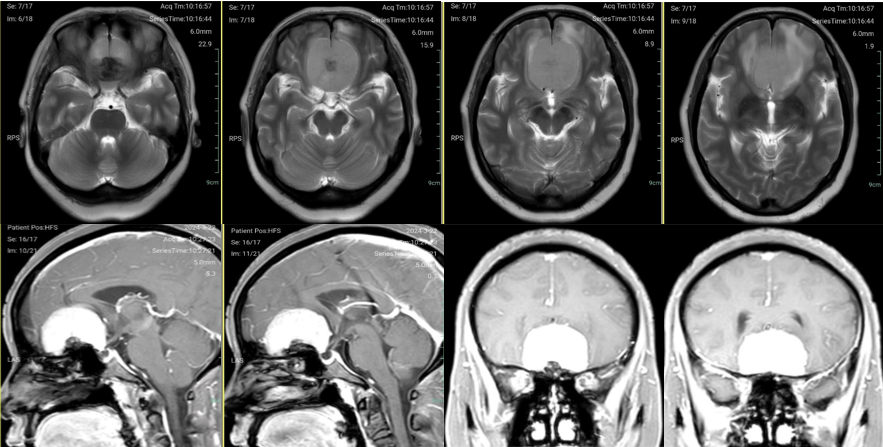

颅脑磁共振增强扫描示前颅底巨大脑膜瘤,基底前至鸡冠,后达垂体窝,基底宽。

颅骨冠矢状位重建示前颅底骨质明显增生,额窦发达。

手术前与手术后第十天后颅脑增强磁共振比较:前颅底巨大脑膜瘤影像学切除完全。

术后三个月颅脑强化磁共振显示肿瘤无明显残留。